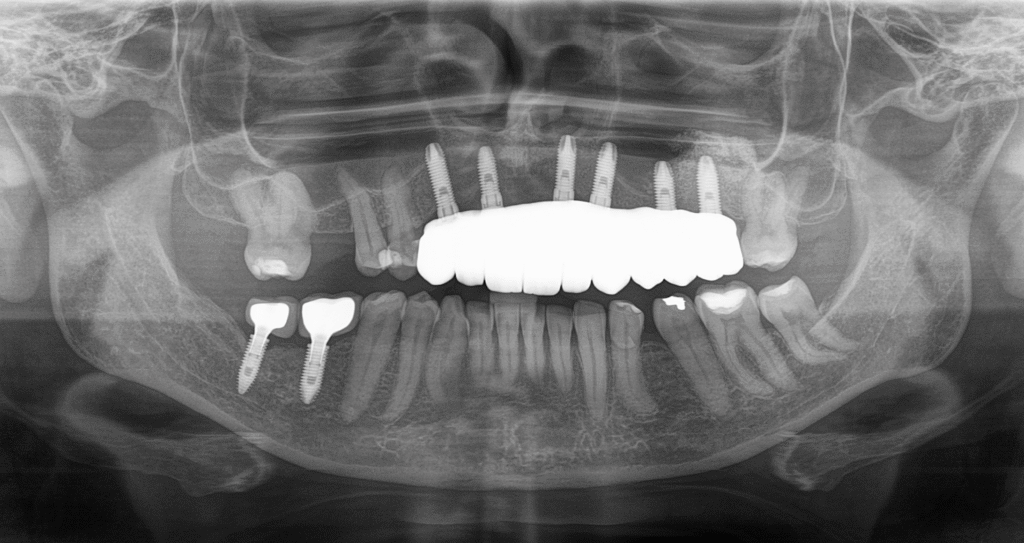

Radiografia panorâmica

Oferece uma visão geral das arcadas e articulações, ideal para avaliar perdas ósseas e dentes inclusos.

Indispensável para planejamento de implantes dentários e cirurgias avançadas. Mostra altura, espessura e densidade óssea.